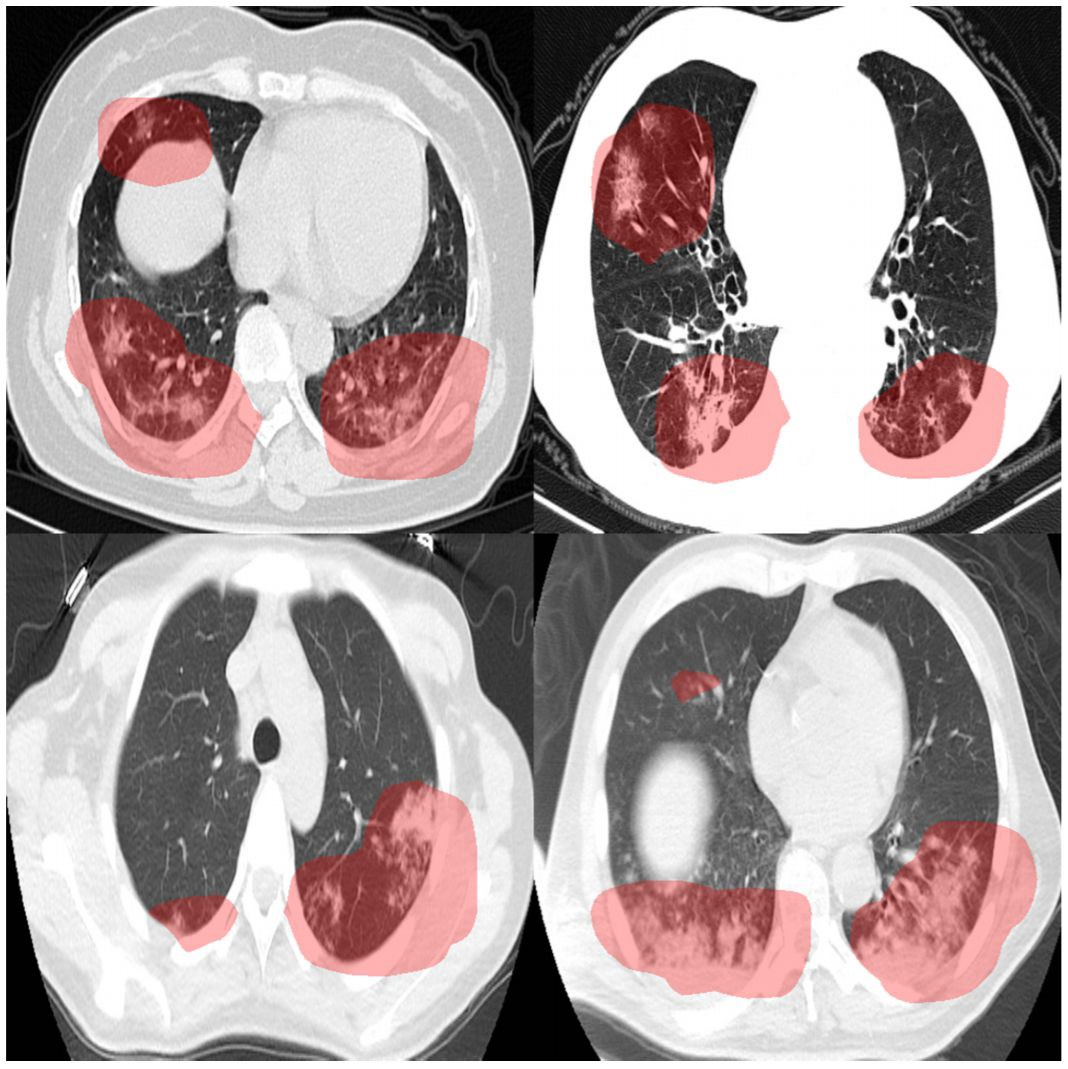

NVIDIA Inception의 회원사 다윈AI(DarwinAI)가 CT 스캔에서 코로나19를 감지할 목적으로 새롭게 개발한 AI 모델이 광범위하고 다양한 시나리오에서 진단 정확도 96%를 기록했습니다. COVID-Net CT-2라는 이름의 이 모델은 캐나다 워털루대학교(University of Waterloo)와 함께 수 개월에 걸쳐 다양하게 생성한 대규모 데이터세트를 이용해 구축되었으며 현재 깃허브(GitHub)에 공개되어 있습니다.

셸던 페르난데스(Sheldon Fernandez) 다윈AI CEO는 “아주 풍부한 데이터를 기반으로 COVID-NET CT-2를 구축한 결과 전혀 새로운 수준의 진단 정확도를 달성했습니다. 광범위하고 다양한 시나리오 전반에서 코로나19 민감도와 양성예측치가 96%를 넘어섰죠”라고 설명합니다.